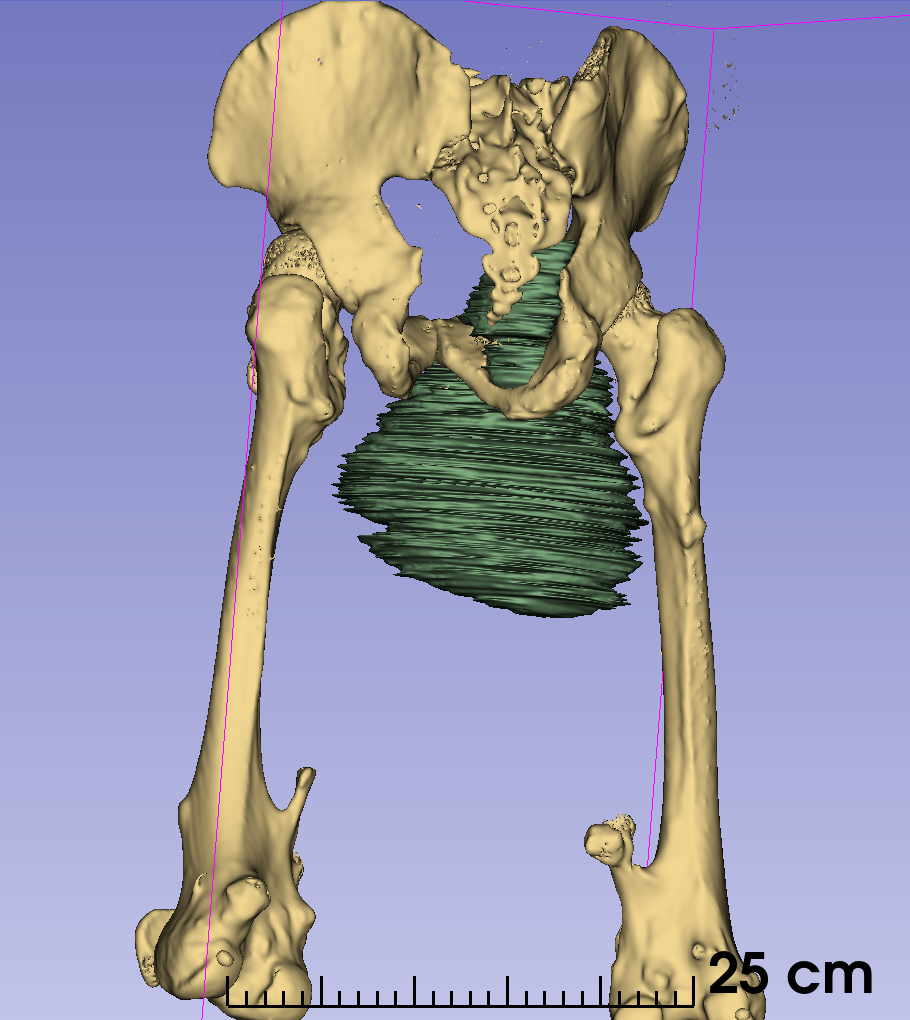

通过3D建模的精准评估,小王右耻骨软骨肉瘤体积达到了1600立方厘米(1600623.71立方毫米),肿瘤下极自右大腿中段向上,内侧贴大腿皮肤,外侧推压内收肌群及股动静脉,穿过骨盆右闭孔,紧贴右髋臼内侧壁生长,骨盆内占位部分推压膀胱。

图片 8.png图片 10.png图片 9.png

3d建模

患者的肿瘤累及右侧耻骨上下支(Enneking Ⅲ区),预计截骨范围为耻骨联合到耻骨上支、耻骨下支到坐骨体内侧。由于肿物体积巨大,无论采用髂股入路还是髂腹股沟入路,单纯前路手术很难暴露坐骨及髋臼后柱结构,而在前路强行提拉推压肿物则会增加肿瘤破裂的风险。通过延伸Gibson入路,可以清晰的显露坐骨支,完整地显露截骨边界,降低肿瘤破裂及血管损伤的风险。由于该部分区域为非负重区,因此,无需进行骨盆环重建,但需要注意盆壁的修补,预防盆腔器官受重力作用下垂相关并发症。